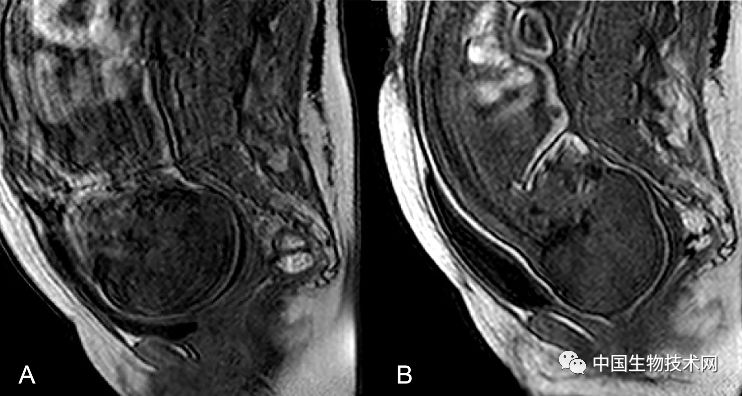

胎头成型和第二产程期间的头部形状变化 图片来源:《PLOS ONE》

近日,法国克莱蒙奥弗涅大学的研究人员利用三维磁共振成像(MRI)技术,拍摄了显示胎儿大脑和头骨在分娩前通过产道时如何改变形状的三维图像。该研究结果近日已发表在《PLOS ONE》上。

众所周知,胎儿头部在出生时是会发生形状改变的,这些变化被称为“胎头成型”,发生在分娩的第二阶段(第二产程)——当胎儿离开子宫通过产道时经历这些变化。然而,研究人员对胎头成型的细节仍知之甚少,只有一项先前的研究曾捕捉到这一过程的图像。

在这项新研究中,为了证明和描述胎头成型和分娩过程中大脑形状的变化,Olivier Ami博士领导的研究团队使用三维MRI捕捉了7名胎儿在分娩前和第二产程中头骨和大脑的详细图像。该分析揭示了所有7名胎儿在第二产程都有胎头成型,其中颅骨的不同部位存在不同程度地重叠。其中5名新生儿的头骨和大脑形状恢复到出生前的态势,但另外2名新生儿的头骨和大脑形状仍在变化。胎头成型程度最高的三名新生儿中有两名是通过紧急剖腹产手术分娩的,另一个是通过阴道分娩的。

图片来源:《PLOS ONE》

总的来说,该研究结果表明,胎儿在出生时承受的颅骨压力比之前所认为的要大,这可能是许多顺产新生儿出现无症状性脑出血和视网膜出血的潜在原因。

Ami补充道:“在阴道分娩的过程中,胎儿的大脑形状会根据颅骨重叠的程度发生不同程度的变形。大多数新生儿出生后颅骨成型不再明显。有些头骨顺应变形以便于分娩,而另一些头骨不容易顺应变形。”